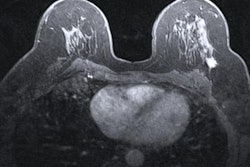

At the RUMC, different MRI protocols are used for breast imaging with MRI, depending on the purpose. Staff use a 20-minute MRI protocol for diagnostic imaging and an eight-minute abbreviated MRI (abMRI) protocol for screening. The motivation to implement abMRI is to increase cost-effectiveness.

"The idea is to be able to scan more women within the same timeframe with MRI," Koco explained. "This would therefore allow greater access to MRI screening for more women and reduce the time women have to spend inside the MRI scanner (anxiety, claustrophobia, lying still)."

With the abbreviated MRI protocol, three patients can be scanned per hour, and if diffusion-weighted imaging is omitted, it is also possible to scan four patients in one hour. Another important benefit is that the MRI scanner is almost continuously in use, she added.